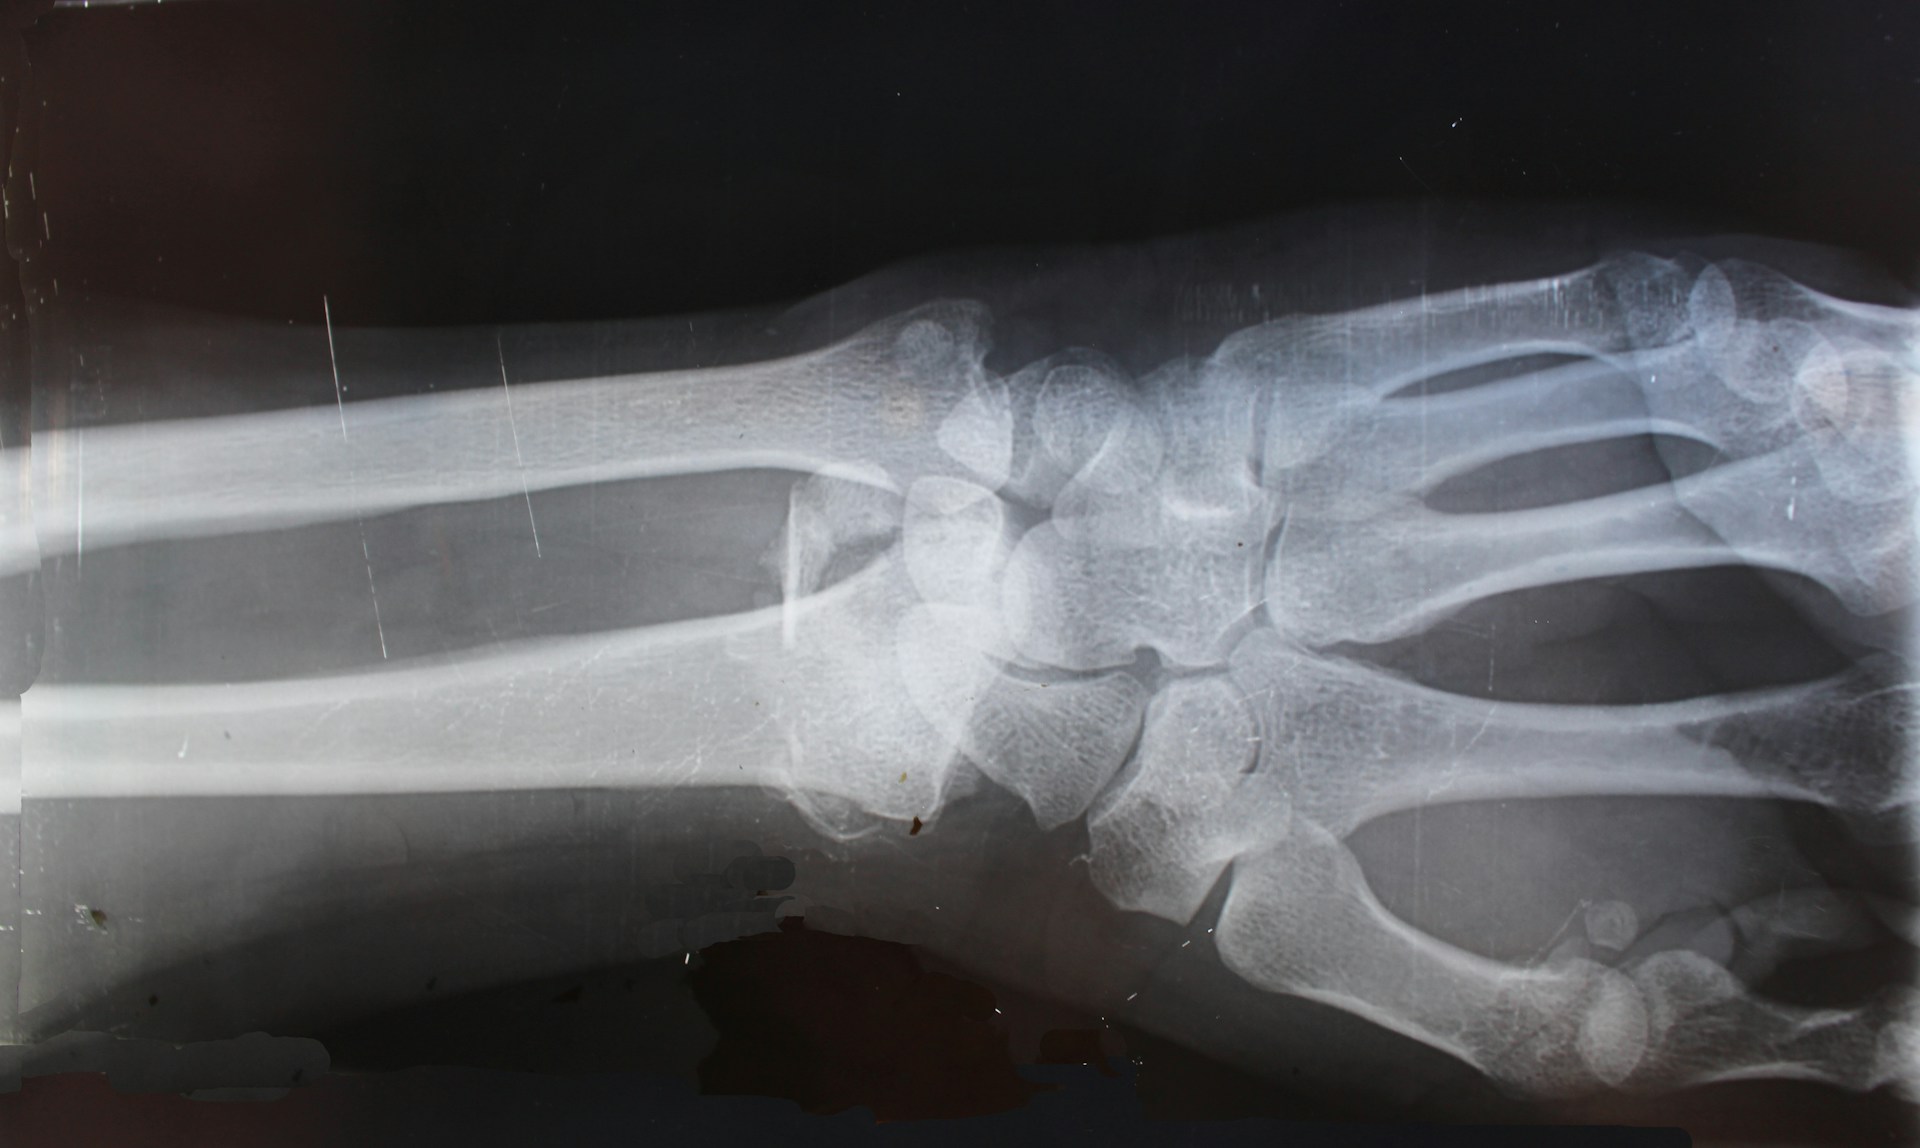

Rehabilitation after fracture

Fracture / Broken Bones Rehabilitation (18+)

Exercise advice and rehabilitation after fractures. For adults only.